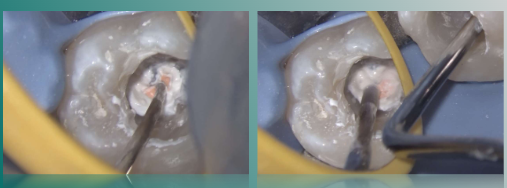

根管内注入生物陶瓷SP糊剂

近远中根管内放入牙胶尖

携热器切断至距很尖4-5mm处

垂直加压根管内牙胶

热牙胶回填近中根管,垂直加压。

远中根管回填热牙胶,垂直加压,将牙胶压入狭区。

远中根管继续回填热牙胶,垂直加压C形区域,将牙胶压入狭区。

远中根管继续回填热牙胶,少量多次回填,耐心仔细加压。

超声清洁髓腔

根充后髓腔内状态